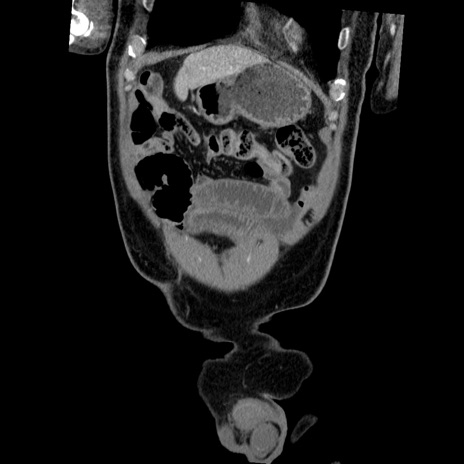

症例22(冠状断像)

【症例】50歳代男性

【主訴】腹痛

【現病歴】AVMからの被殻出血のため回復期リハ病棟入院中。 本日午後3時頃急に下腹部痛が出現した。

【既往歴】AVM、被殻出血、虫垂炎、高血圧

【身体所見】意識晴明、左半身不全麻痺、会話の理解は良好、36.5°C、腹部:膨隆、全体に板状硬、下腹部正中に圧痛点あり、反跳痛-、筋性防御不明、右下腹部にope scar

【データ】WBC 9400、CRP 0.06